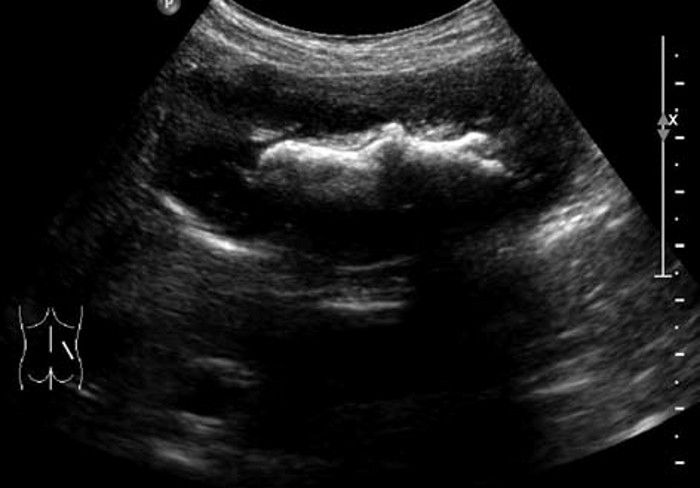

肾结石的超声图像,肾结石超声诊断及鉴别 4. 肾结石合并积水:近端扩张积水,如肾盏颈部梗阻引起肾盏扩张,肾盂输尿管连接部梗阻则表现肾盂,甚至肾盏扩张积水。如发现有随体位改变移动的小结石,提示下方多有结石嵌顿,应追踪扫查,明确引起梗阻的原因。

典型病例

患者,男,12岁,因运动后多次突发腹痛,腹痛不能缓解并伴有恶心,面色苍白来院就诊,尿常规检查可见红细胞。超声检查显示:双肾大小形态大致正常,轮廓清,包膜光滑,实质回声尚均,呈低回声。右肾未见明显分离,左肾集合系统分离约1.1cm,左肾内可见0.9cm×0.7cm强回声,后方有声影。

超声提示:左肾集合系统分离,左肾结石。